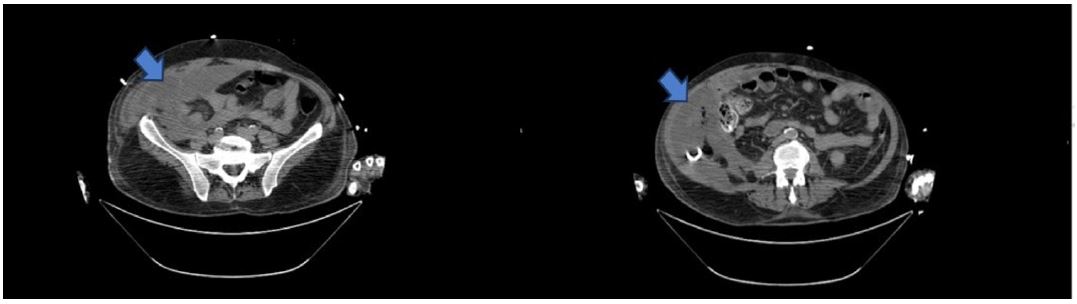

Three days later, the patient was extubated and transferred to a hospital closer to his residence. Upon arrival, clinical deterioration occurred, characterized by cardiovascular and neurological dysfunction, necessitating reintubation. The previously purulent abdominal drainage had changed to enteric characteristics, prompting a new CT scan, which indicated a multiloculated retroperitoneal collection extending from the right flank to the pelvis, suggestive of bowel perforation (Figure 1). The patient was taken for laparotomy, during which a large infected retroperitoneal hematoma was identified and extensively debrided and bowel perforation was ruled out. Two drains were placed in the right flank and peri-hepatic space. The surgery proceeded without complications. However, on the first postoperative day, a high output of biliary content was noted in the abdominal drains. Bilirubin analysis of the drain’s contents confirmed the presence of biliary drainage.

Figure 1: Abdominopelvic CT scan previous to the exploratory laparotomy: Evidence of a multiloculated retroperitoneal collection (arrow) extending from the right flank till the pelvis with a heterogeneous aspect.